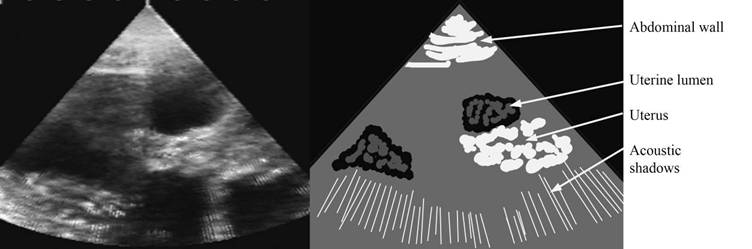

Pseudopregnancy – around 35 days

Note while there appears to be black holes there are no embryos

Sometime the uterine lumen may be filled with a “grains”

repro draw pseudopreg label.jpg